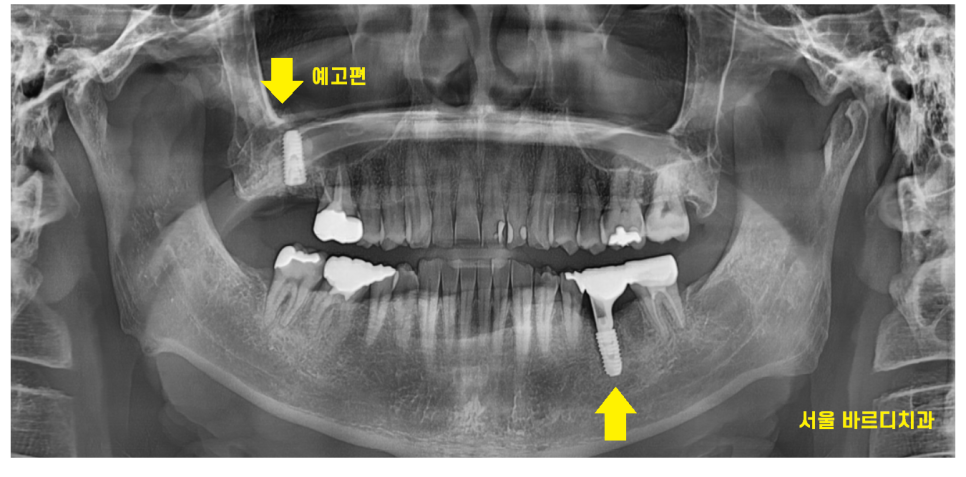

환자분께서 직장생활 때문에

시간 내기가 어렵다 하셨습니다.

그래서 치아뿌리 파절된 부위를 발치

그리고 당일 바로 임플란트를 하기로

고덕역 치과에서 상담해드렸습니다.

고덕역 치과 방문하신 당일

진단, 상담, 치료까지 완료해드렸습니다.

치아뿌리 파절 제거

그리고 임플란트까지~~

24.01.16

치아 뿌리 파절된 치아를 치료하는 동안

반대편 치아에도 문제가 생겼는데요.